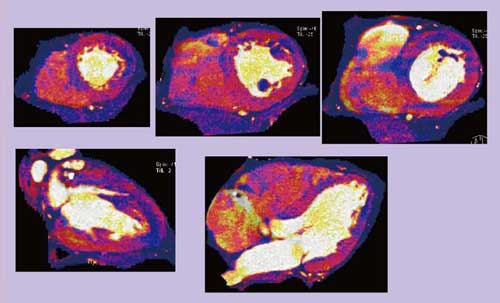

70歳,男性,3枝PCI後の症例で,再狭窄が疑われた。DEイメージングによる120kVの合成画像から作成した冠動脈CT(図2)では,多くの石灰化やステントがあるため再狭窄の有無は明らかではなかったが,ヨード強調マップ(画像)(図3)では心尖部側壁寄りや後位前壁に低灌流域が認められ,SPECTでも同一の場所で再分布を伴う虚血が認められた。このようにDEイメージングを用いることで,非常にクリアに虚血を描出できる可能性がある。

図3 図2の症例のDEイメージング(ヨード強調マップ)

●Case4:高心拍数への対応

65歳,女性,労作時胸痛,撮影時心拍数(HR)が75bpmの症例である。HRが高いため100kVと140kVの合成画像再構成がうまくいかず,ヨード強調マップ(画像)では数値エラーが虚血のように見えている(図4)。われわれの経験では,HRが上がると,アーチファクトにより画質が劣化することが明らかになった(図5)。時間分解能の不足や低電圧(100kV)側のノイズが原因となり,heartPBVソフトウェアでの再構成エラーに遭遇することも多い。